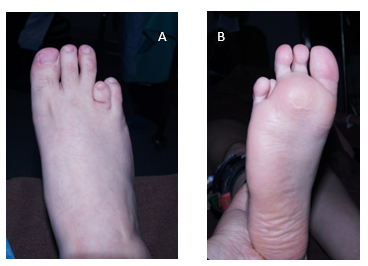

CASO 1: Paciente de 40 años, sexo femenino, portadora de un acortamiento congénito del cuarto metatarsiano bilateral y asimétrico. Consultó por un problema estético y metatarsalgia a nivel de la cabeza del cuarto metatarsiano del pie izquierdo. Al examen físico se destaca que tiene un cuarto radio corto, con un dedo elevado, sin lesiones en dorso, flexible y subluxado con un leve varo. Sin alteraciones neuro-vasculares distales y pulsos presentes. El retropie tenía alineación neutra. Las articulaciones tibiotarsiana y subastragalinas eran móviles e indoloras. No se observan desviaciones asociadas de los otros dedos, que son flexibles.

En la planta del pie se constata una hiperqueratosis a nivel de la cabeza del cuarto metatarsiano. El pie derecho, era asintomático, si bien tenía un cuarto radio corto de menor magnitud con respecto al otro pie, el dedo estaba en mejor posición, sin callosidades. (Figura 1).

Figura 1: A y B: frente y perfil. Presentación clínica del paciente. Se observa una braquimetatarsia del cuarto radio.